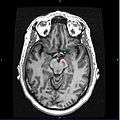

Section through superior colliculus showing Substantia nigra. | |

Horizontal MRI (T1 weighted) slice with highlighting indicating location of the substantia nigra.